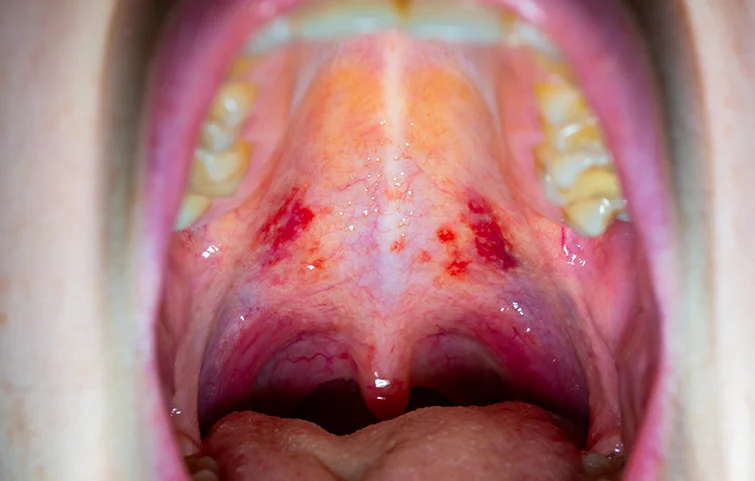

Mouth cancer, also known as oral cancer, refers to cancer that develops in the tissues of the mouth, including the lips, gums, tongue, inner lining of the cheeks, roof and floor of the mouth, and the tonsils. It can occur as a single tumor or multiple lesions and is classified under head and neck cancers.

• Sore or ulcer in the mouth that doesn't heal

• White or red patches in the mouth